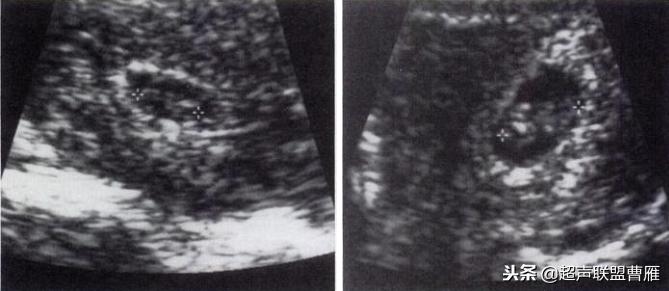

5周+ 、6周+ 声像图

孕7周左右(胚芽11mm 卵黄囊)

胎芽 卵黄囊 心管搏动信号

宫内早孕 (7周左右)

正常宫内胚胎组织、卵黄囊